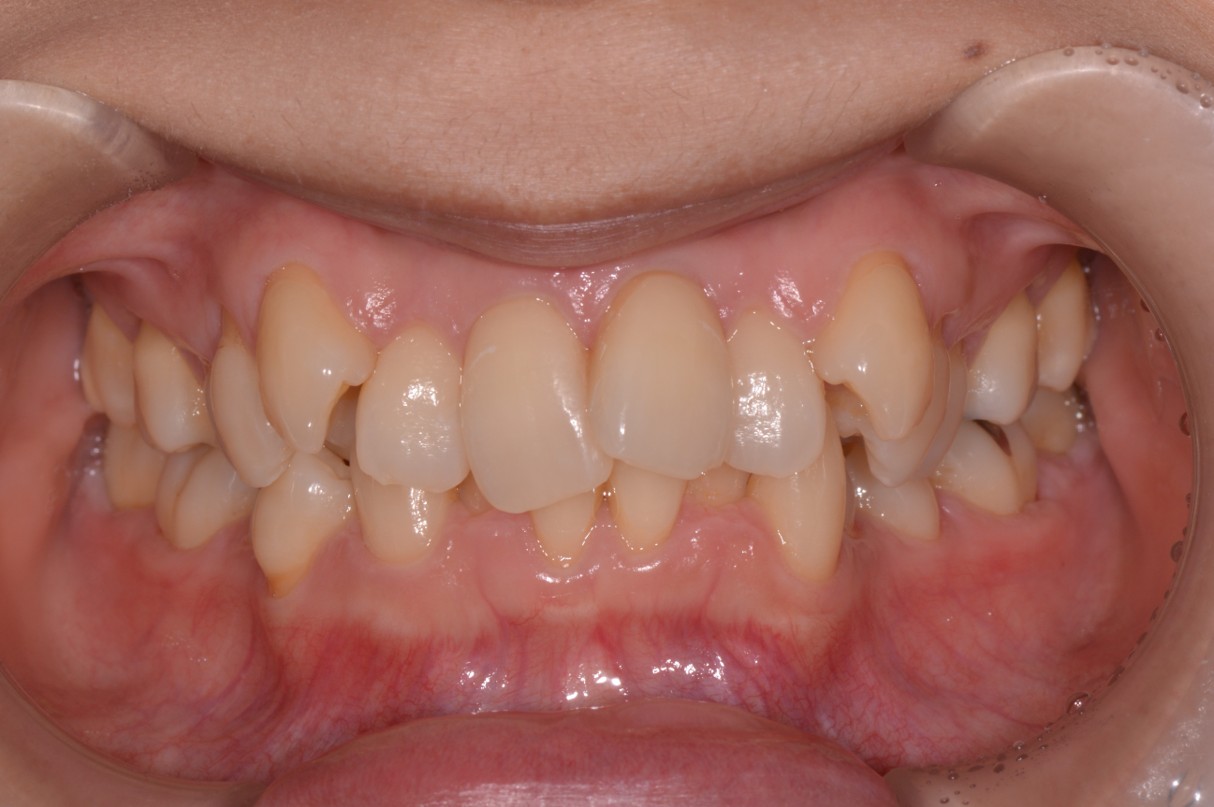

症例1

| 項目 | 詳細 |

|---|---|

| 患者様データ | 30代 女性 |

| 来院時の主訴 | 「上下のガタガタ歯並びと噛み合わせが気になる。」 |

| 矯正法 | 上の歯2本を抜歯しての矯正 |

| 通院期間 | 2年9ヶ月 |

| 治療費 | 総額:1,070,000円(税抜) 【内訳】 精密検査50,000円、メタルワイヤー矯正800,000円、月に1度の調整料5,000円、後戻り防止のリテーナー35,000円×2 |

| リスクと副作用 |

①歯を動かす事による痛みがあります。また、装置に慣れるまでは、口内炎ができやすいです。 ②歯肉が退縮するリスクがあります。装置が全ての歯に付くので、ハミガキが難しくなります。 ③長期的なメインテナンスが必要 |

| ここがこだわりのポイント!☝ |

この患者様の場合、歯並びのガタガタが強かったことや、抜歯したスペースを埋めるのに時間がかりました。ホームケアも大変だったと思いますが、とてもきれいな歯並びに改善することができました。 |